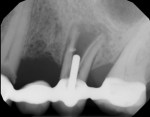

The patient's chief concern was a failing bridge in the upper left posterior sextant. Tooth No. 11 was severely decayed, necessitating endodontic treatment, post, and crown to salvage. Tooth No. 13 had a vertical fracture, which left it with a hopeless prognosis (Figure 1). The treatment plan included the extraction of tooth No. 13 and placement of dental implants in position Nos. 12 and 13. Traditionally, the clinician would have considered a two-stage approach for tooth No. 13, which typically would require 3 to 6 months of hard- and soft-tissue maturation prior to implant placement.